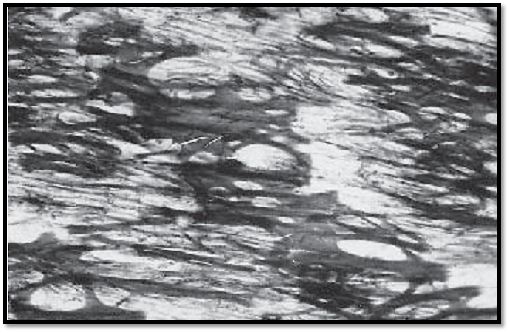

This cross-section of the tunica media from the descending aorta shows strong, in some places undulating elastic membranes (stained blue-violet). In a vertical section, they appear as fibers with intertwined muscle cells. At their insertion sites, the muscle fibers create the image of brush strokes. The myocytes encircle the aorta, forming right- and left-handed spirals. This creates a fishbone pattern in a cross-section. In this arrangement, the smooth muscle cells can regulate the tensile force of the elastic fiber network . The collagen connective tissue is stained green. A vessel of the vessel wall 1 ( vas vasis ) is visible in the left corner of the image.

1 Vessel with erythrocytes

2 Smooth muscle cells, myocytes

Stain: Masson-Goldner trichrome; magnification: × 400